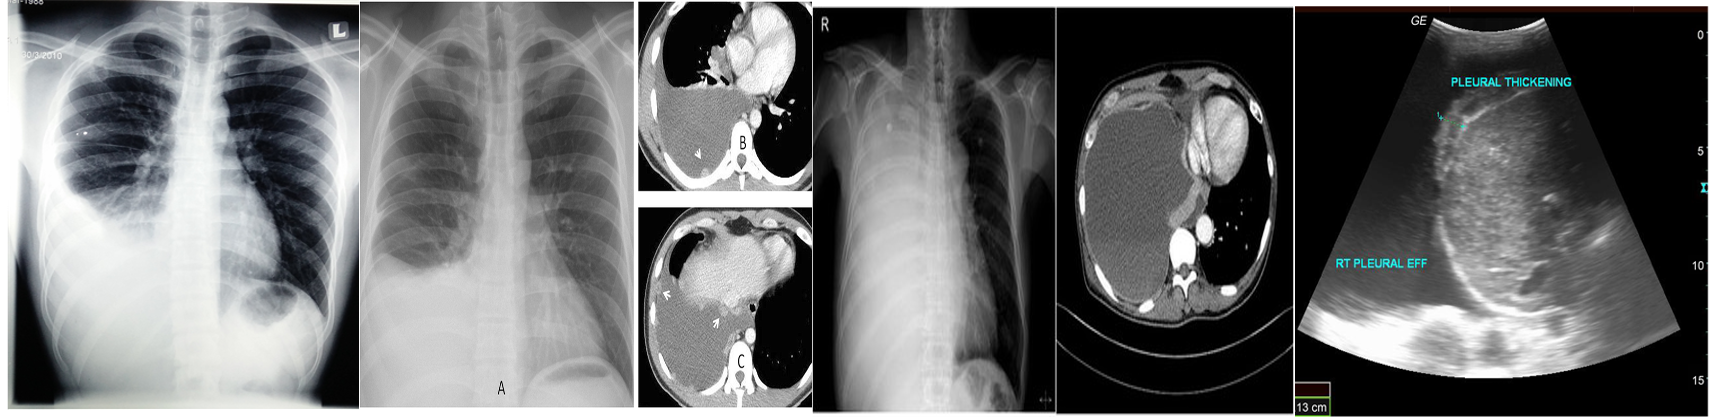

Imaging to confirm the diagnosis:

Chest X-ray: Lateral decubitus view (most sensitive): > 200 ml.

- Unilateral blunting of the costophrenic angle

- Homogeneous density with a meniscus-shaped margin (meniscus sign)

- Complete opacification of the lung (Large effusion) and Mediastinal shift and tracheal deviation.

Ultrasound: Quick, bedside assessment, if planning thoracentesis.

- Very sensitive: 20 ml. Hypoechoic collection.

- Detection of pleural thickening and pleural nodules.

CT: Gold standard for small effusions.

- Guiding placement of indwelling pleural catheters.

- Directed thoracentesis of a loculated effusion.

- Suspected parenchymal or pleural pathology. contrast CT is now increasingly performed to investigate the underlying cause, particularly for exudative effusions